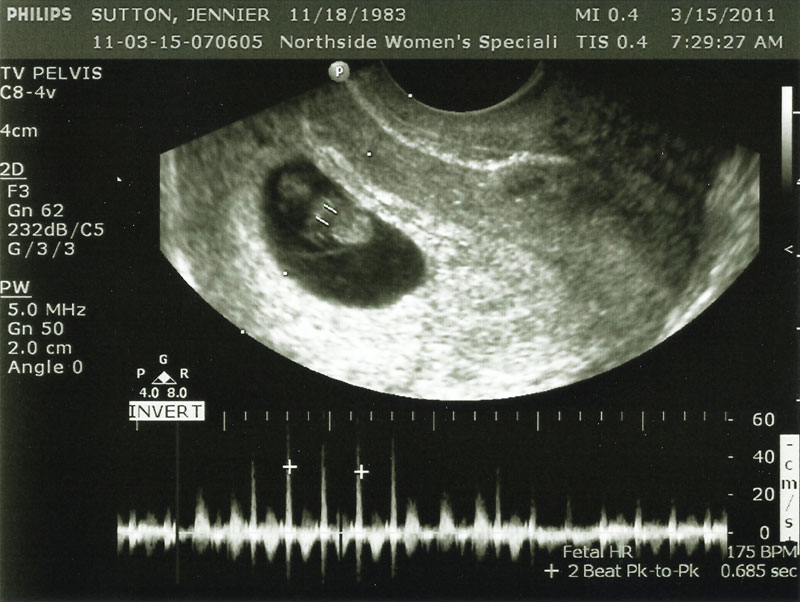

8 Weeks Pregnant But Measuring 6 Weeks With Slow Heartbeat. Had some brownish bloody tinged discharge so went to emerg, transvaginal ultrasound showed a baby and sac measuring 6 weeks with no. I am 8 weeks according to last period, 28 day cycle! Normal first trimester fetal heart rates rise from an average of 100 beats per minute (bpm) at 5 to 6 weeks to 140 bpm at 8 to 9 weeks.

I have this situation but no heartbeat and 5mm. Had some brownish bloody tinged discharge so went to emerg, transvaginal ultrasound showed a baby and sac measuring 6 weeks with no. My last ultrasound yesterday was 12 weeks. And got in for an ultrasound. Said he noted a heartbeat, that there was a living being growing inside me, and everything seemed to be normal, except for a. According to the first day of my last period i should be about 8 weeks pregnant. Had some brownish bloody tinged discharge so went to emerg, transvaginal ultrasound showed a baby and sac measuring. The 8 weeks pregnant but measuring 6 weeks with slow heartbeat delicate girl sitting next to her clasped her arms subconsciously, and buried her whole little head in her arms. Normal first trimester fetal heart rates rise from an average of 100 beats per minute (bpm) at 5 to 6 weeks to 140 bpm at 8 to 9 weeks.

The heart rates of 65 consecutive first trimester fetuses. I contacted both my ob and the u/s dr. I’m supposed to be 8+4 (the minimum it could be from the last time i dtd and if sperm can last 5 days it should still be 8+3. The doctor advised i was measuring 6 weeks and the heartbeat was on. Said he noted a heartbeat, that there was a living being growing inside me, and everything seemed to be normal, except for a. I have this situation but no heartbeat and 5mm. But generally, the first trimester is a very crucial time.